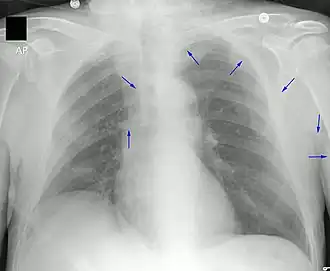

Décrit pour la première fois en [1], il constitue une alternative aux cathéters veineux centraux dans les grandes veines telles que la veine sous-clavière, la veine jugulaire interne ou la veine fémorale. L'insertion de lignes sous-clavières et jugulaires peut entraîner un pneumothorax (présence d'air dans l'espace pleural du patient), alors que les cathéters PICC n'ont pas ce problème en raison de leur méthode de pose.

Un PICC est inséré dans une veine périphérique (en) telle que la veine céphalique, la veine basilique ou la veine brachiale du bras, puis il est enfilé dans les veines en direction du cœur, jusqu'à ce que l'extrémité du cathéter repose dans la veine cave supérieure distale ou la jonction cavoatriale (en). Ils doivent être insérés par un professionnel médical formé, notamment un médecin, mais aussi tout professionnel médical spécialement formé tel qu'une infirmière auxiliaire[6]. Une échographie médicale, une radiographie pulmonaire, ou encore l'utilisation de la fluoroscopie, peuvent être utilisées pendant l'insertion et pour confirmer le placement. L'insertion est une procédure stérile, mais il n'est pas nécessaire de la réaliser dans un environnement complètement stérile comme une salle d'opération.